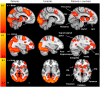

Pain-related anxiety and fear are associated with increased difficulties in attention, increased awareness of pain, impaired disengagement from pain, and can moderate the effects of attentional coping attempts. Accurately assessing the direct impact of pain-related anxiety and fear on pain behavior has proved difficult. Studies have demonstrated no or limited influence of pain-related fear and anxiety on behavior but this may be due to inherent problems with the scales used. Neuroimaging has improved the understanding of neural processes underlying the factors that influence pain perception. This study aimed to establish if a Picture and Imagination Task (PIT), largely developed from the Photographs of Daily Activity (PHODA) assessment tool, could help explore how people living with chronic pain process information about daily activities. Blood oxygenation level dependent (BOLD) functional magnetic resonance imaging (fMRI) was used to compare brain responses in patients with chronic musculoskeletal pain (CMSKP) (n = 15) and healthy controls (n = 15). Subjects were asked to imagine how they would feel mentally and physically if asked to perform daily activities illustrated in PIT. The results found that a number of regions involved in pain processing saw increased BOLD activation in patients compared with controls when undertaking the task and included the insula, anterior cingulate cortex, thalamus and inferior and superior parietal cortices. Similarly, increased BOLD responses in patients compared to controls in the frontal pole, paracingulate and the supplementary motor cortex may be suggestive of a memory component to the responses The amygdala, orbitofrontal cortex, substantia nigra/ventral tegmentum, putamen, thalamus, pallidum, inferior parietal (supramarginal and angular gyrus) and cingulate cortex were also seen to have greater differences in BOLD signal changes in patients compared with controls and many of these regions are also associated with general phobic responses. Therefore, we suggest that PIT is a useful task to explore pain- and movement-related anxiety and fear in fMRI studies. Regions in the Default Mode Network remained active or were less deactivated during the PIT task in patients with CMSKP compared to healthy controls supporting the contention that the DMN is abnormal in patients with CMSKP.